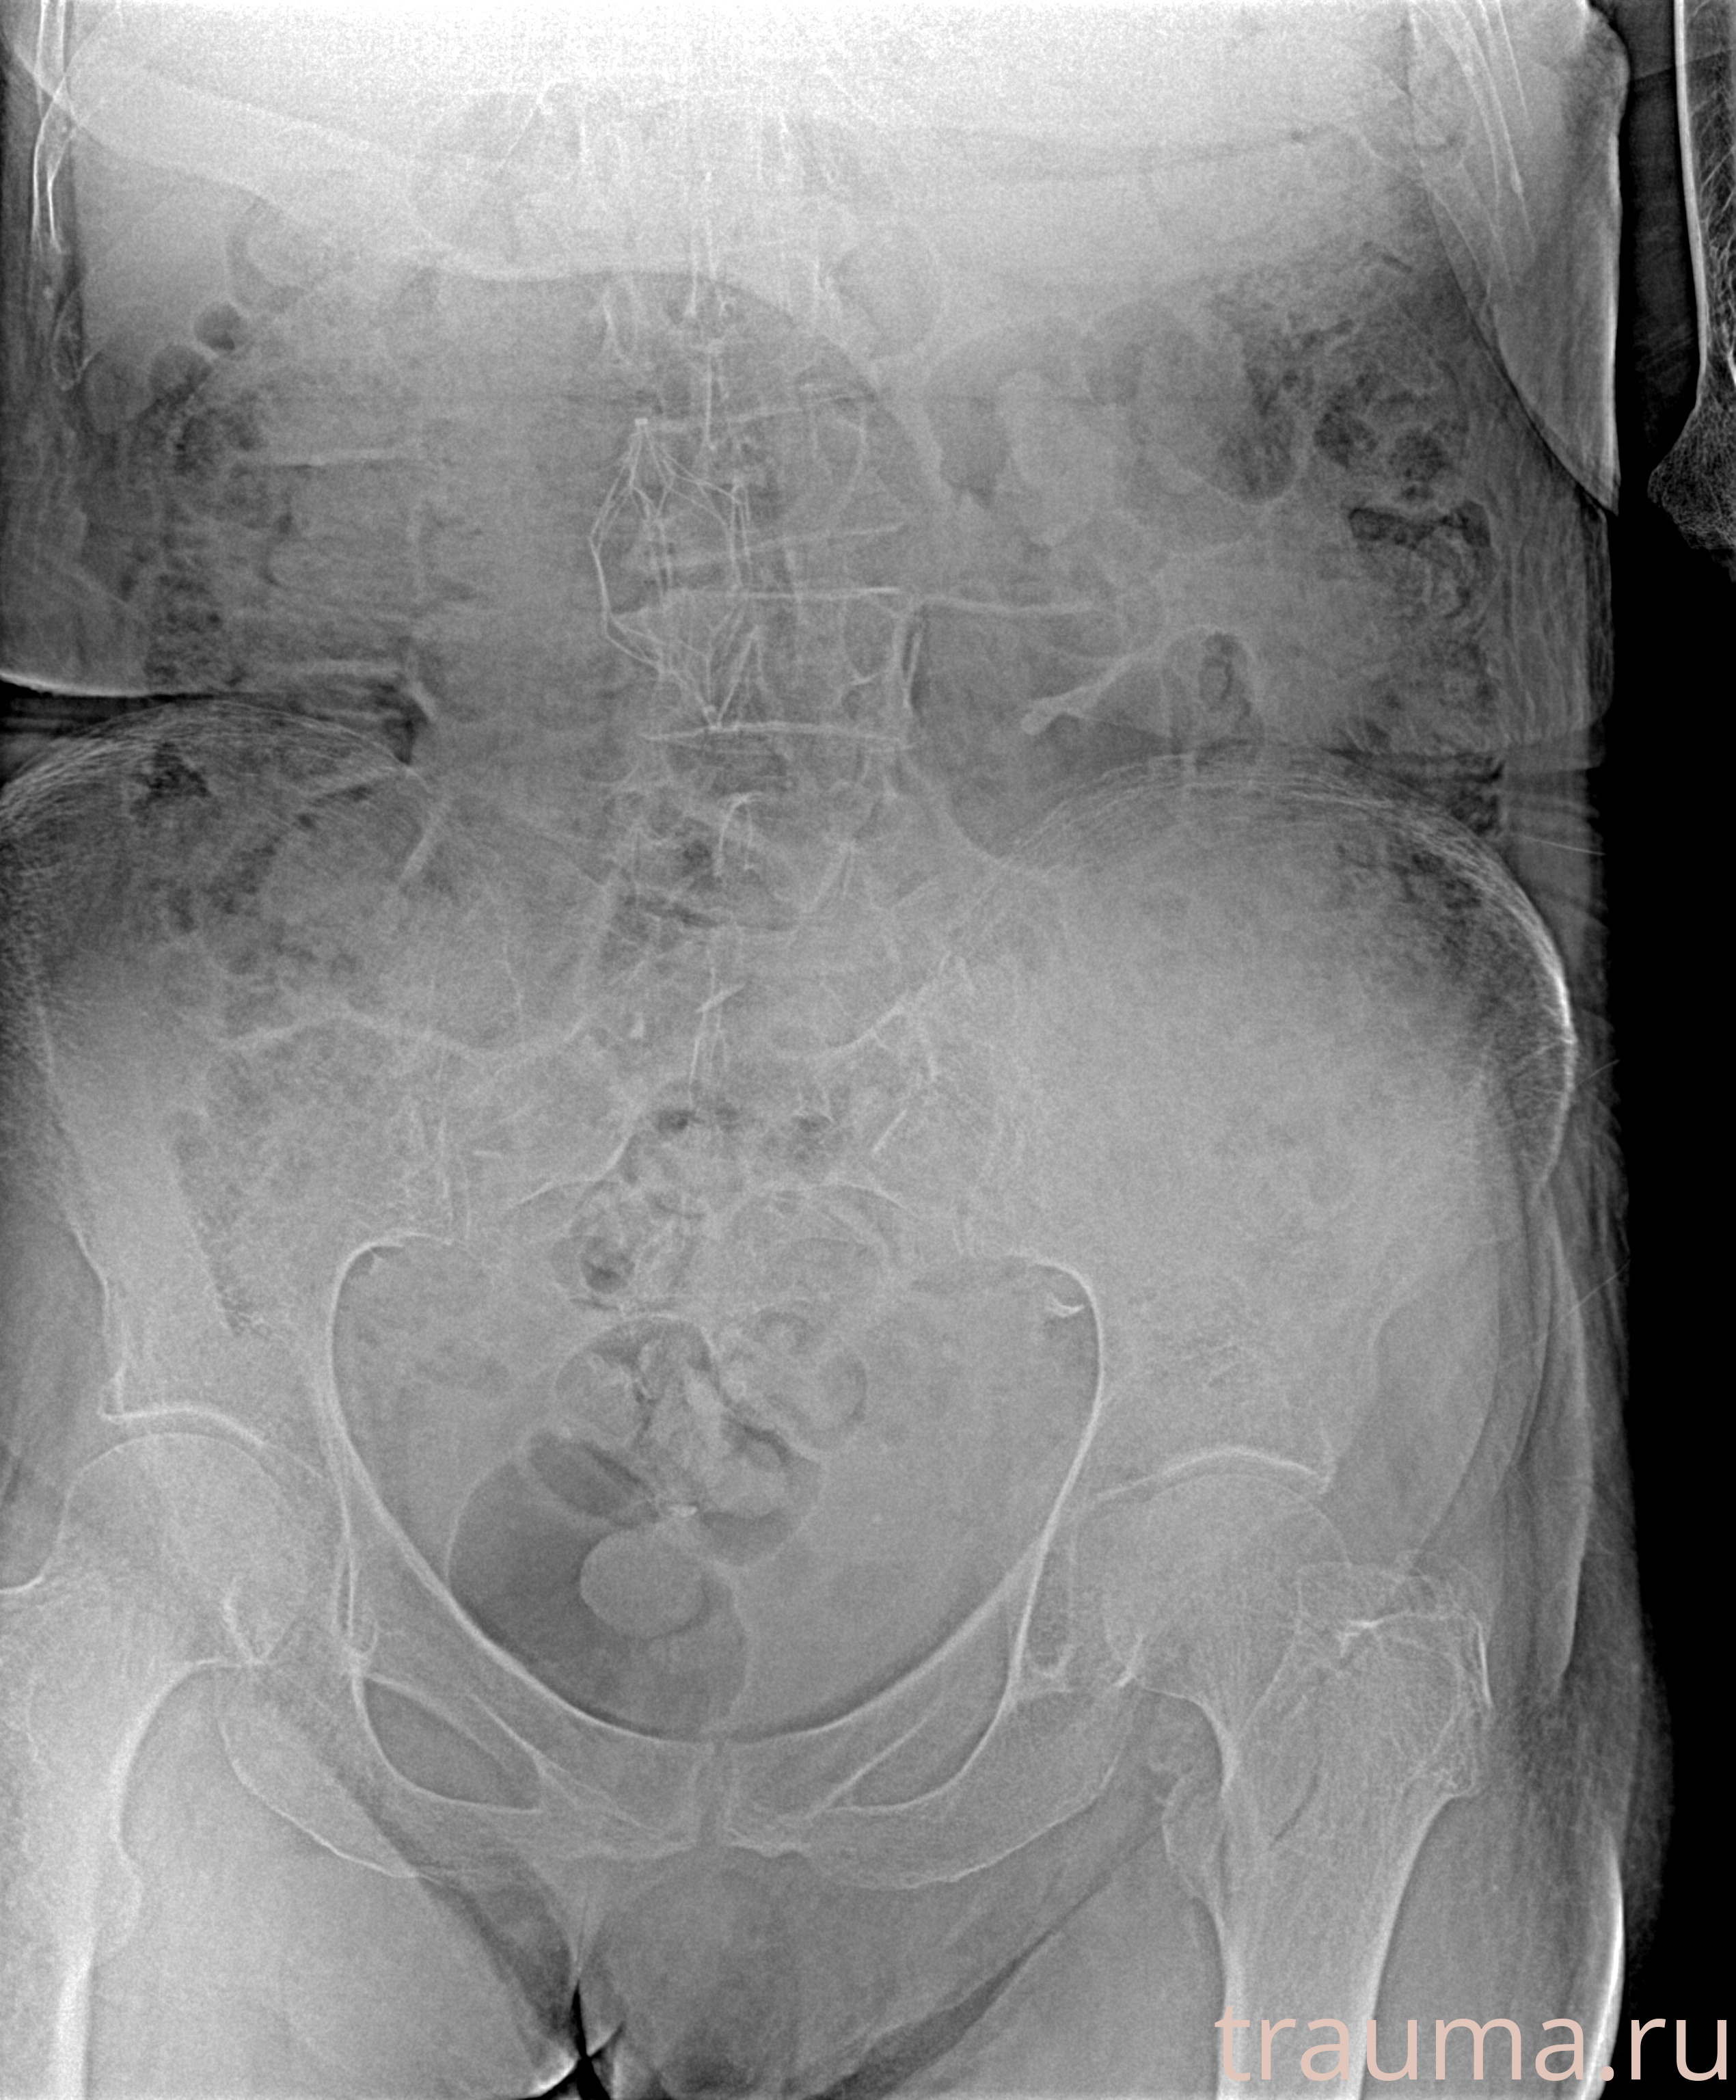

Рентгенограммы

Рентген на дому: по вашему адресу приезжает врач-рентгенолог, травматолог-ортопед с мобильным рентгеновским аппаратом, проводит диагностику травмы или заболевания, делает необходимые рентгенограммы, дает рекомендации по дальнейшему лечению. Получить качественные снимки в домашних условиях возможно благодаря уникальной методике, разработанной МосРентген Центром для института  Склифосовского

при переломе шейки бедра и пневмонии от компании МосРентген Центр - партнера Института имени Склифосовского